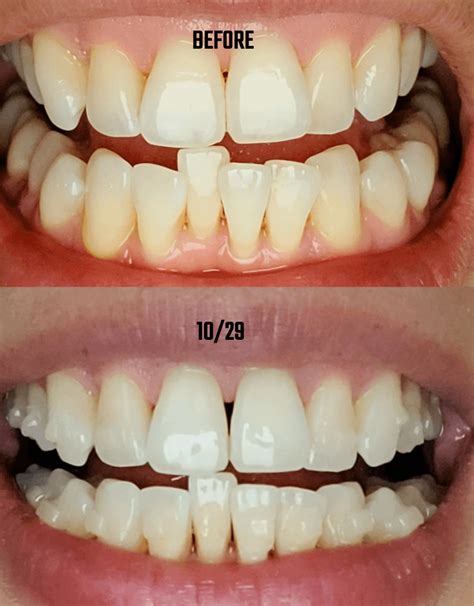

• Scaling and Root Planing: A deep-cleaning procedure that removes plaque and tartar from above and below the gumline and smooths the root surfaces to help the gums reattach.

Preventing Further Progression

• Flawless Oral Hygiene: Proper brushing and daily interdental cleaning (floss, interdental brushes, or water flossers) are non-negotiable to prevent plaque from re-colonizing the treated areas.